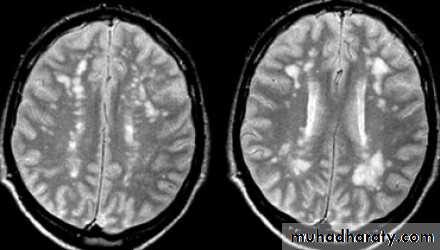

• - MRI:• characteristic abnormalities (plaques) are found in >95% of patients, although more than 90% of the lesions visualized by MRI are asymptomatic

• Plaques are frequently oriented perpendicular to the ventricular surface,

• Plaques are multi-focal within the brain, brain-stem, and spinal cord

• Plaque larger than 6 mm particularly helpful

• Recent plaque show Gd enhancement persists for approximately 1 month

• Old MS plaque remains visible indefinitely as a focal area of hyperintensity (a lesion) on spin-echo (T2-weighted) and protondensity images

Brain MRI films of M.S